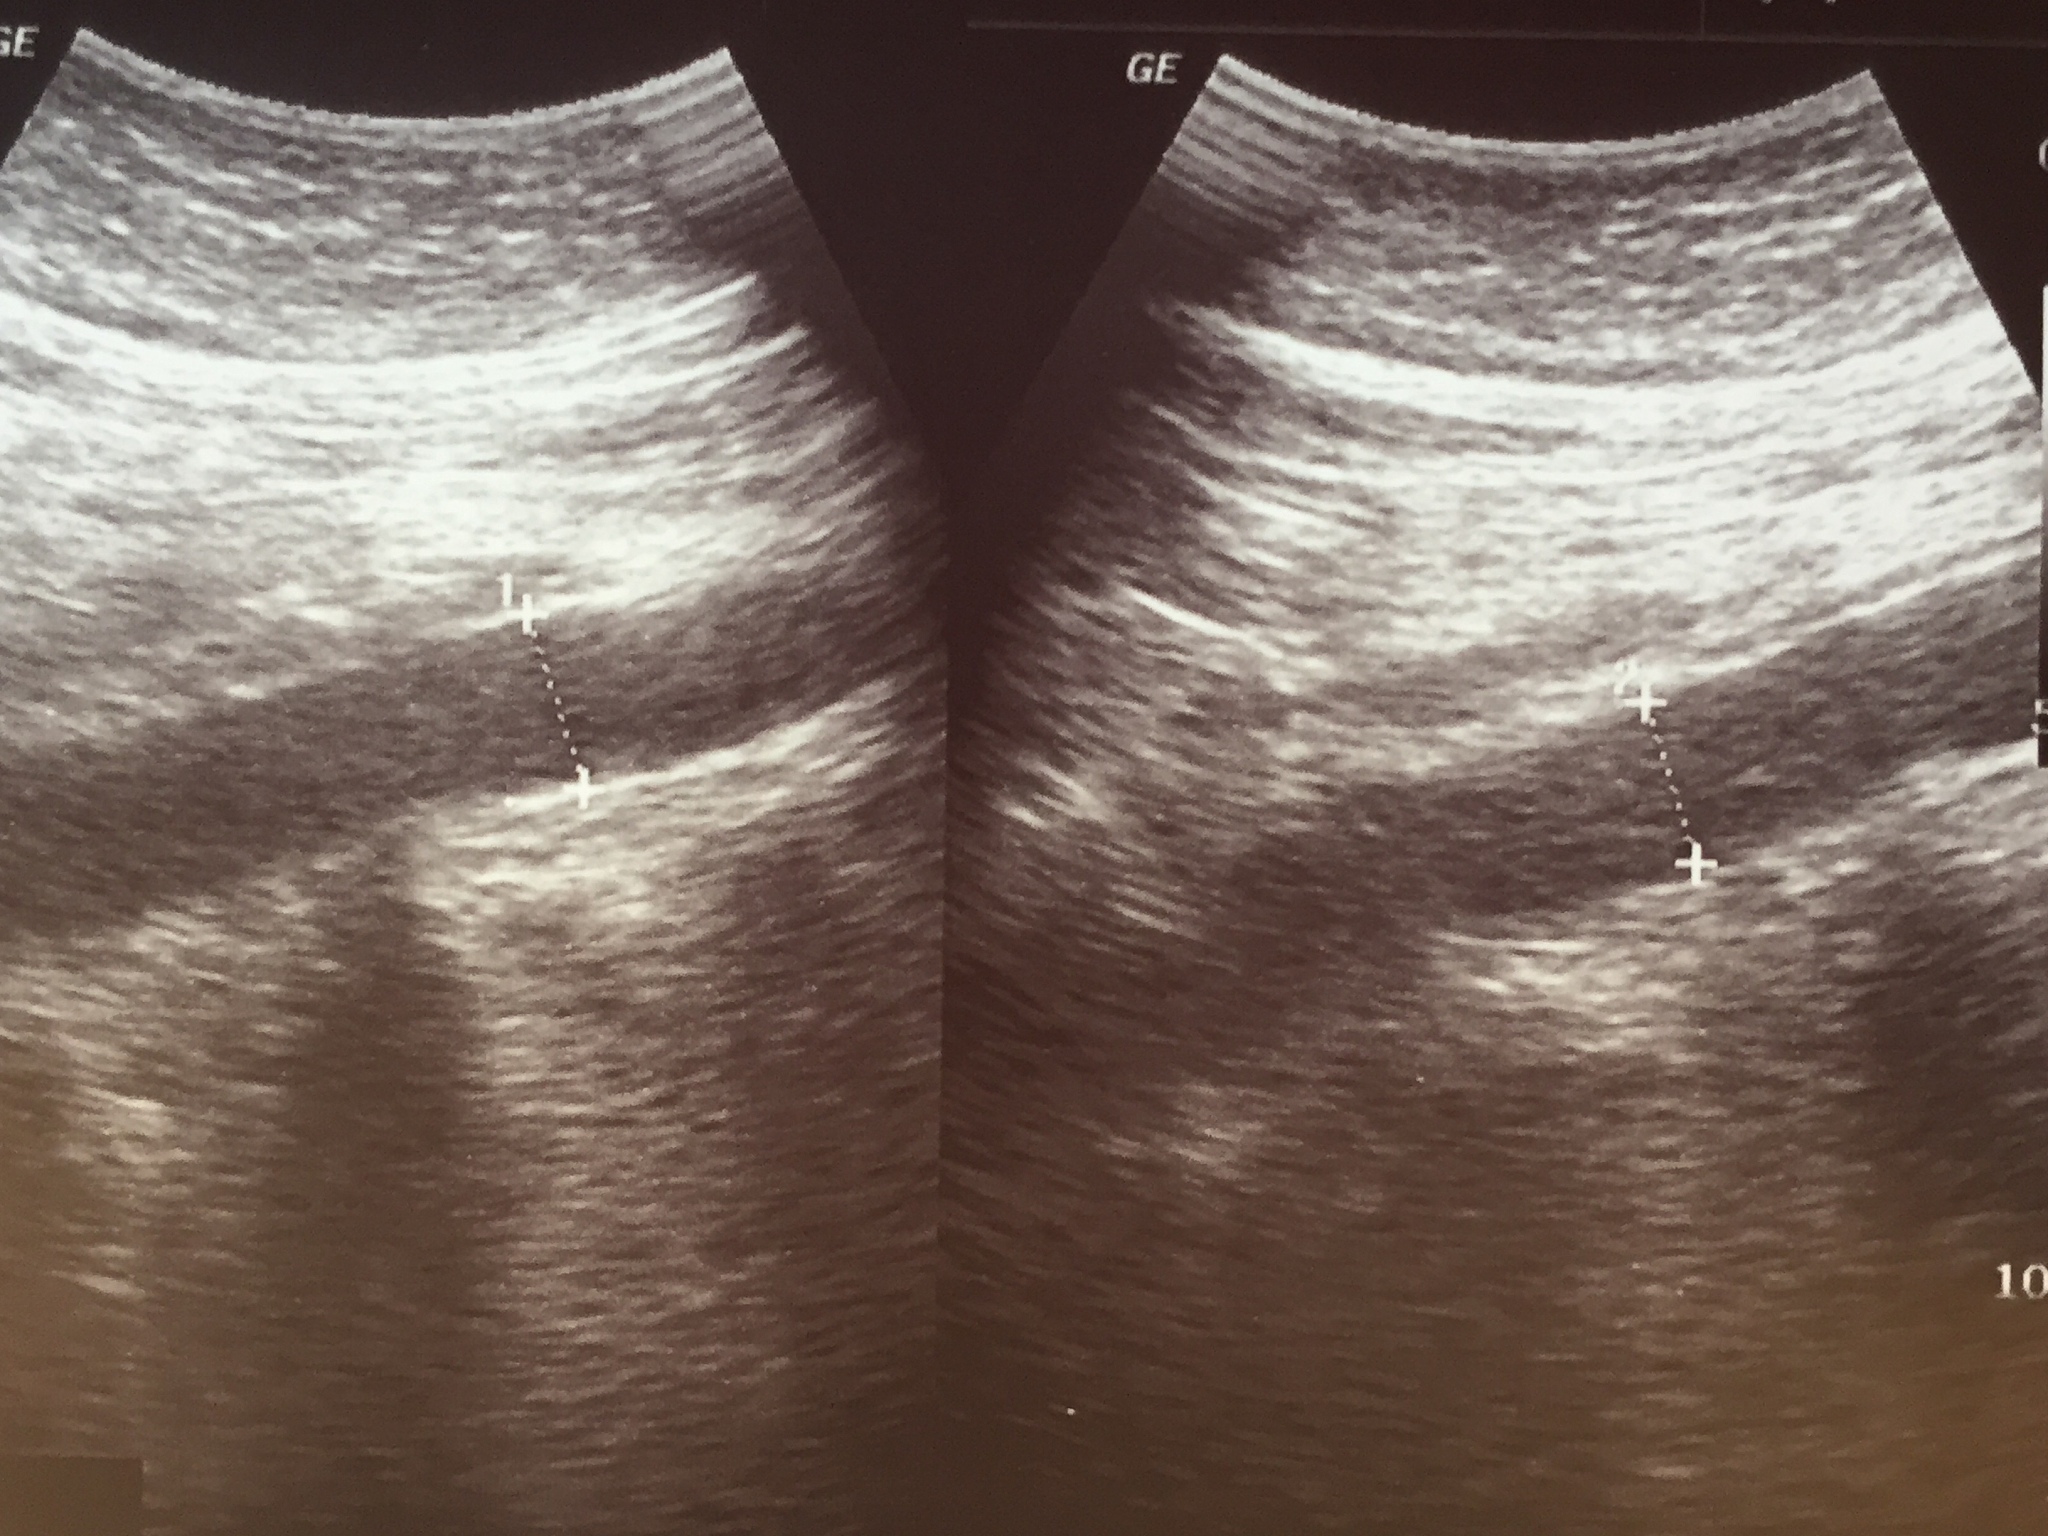

血管内超声诊断导管探头处增加显影性的项目必要性在于提高诊断的准确性和可靠性。增加显影性可以使导管探头在血管内更加清晰地显示,有助于医生更准确地定位和诊断病变,避免误诊和漏诊,从而提高治疗效果和患者生活质量。此外,增加显影性还可以减少操作时间和减轻患者的痛苦和不适感。因此,对于需要进行血管内超声诊断的患者,增加显影性是非常必要的。